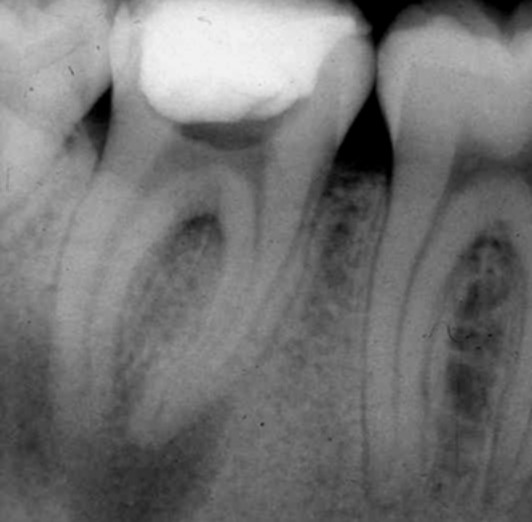

Apertura della corona fino ad arrivare alla camera pulpare (tale trattamento viene eseguito tramite anestesia locale). Si rimuove la polpa e si cercano i canali radicolari del dente, una volta trovati si estirpano i nervi. Si allargano e si puliscono i canali del dente, (tramite strumenti al Nichel titanio o strumenti manuali) prendendo anticipatamente le misure dei canali (per non uscire oltre apice). Si disinfettano i canali e si eseguono vari lavaggi tra un passaggio e un altro per elimininare il fango dentinale. Il medico a questo punto verifica la possibilità di chiudere definivamente i canali o lasciare il dente in prova, inserirendo nei canali un disinfettante e eseguendo una chiusura provvisoria. Al momento di chiudere il dente definivamente, questo viene preparato rieseguendo le misure dei canali da chiudere ed usando per la stessa lunghezza del canale, un cono di guttaperga del diametro necessario. Si scalda il cono in guttaperga e si inserisce nel canale. Durante il trattamento endodondico vengono effettuati una serie di esami radiografici per verificare i risultati, le lunghezze, la forma dei canali.

L'esame radiografico, fondamentale per porre diagnosi in odontoiatria, in endodonzia è irrinunciabile perché è l'unico strumento che ci permette di "vedere" all'interno della radice del dente, è quindi molto importante la possibilità di effettuare lastre con apparecchiature digitali che emettono un quarto della dose di raggi emessa da un radiografico tradizionale e che permettono di conservare la radiografia endorale in una cartella informatica del paziente senza possibili alterazioni nel tempo.